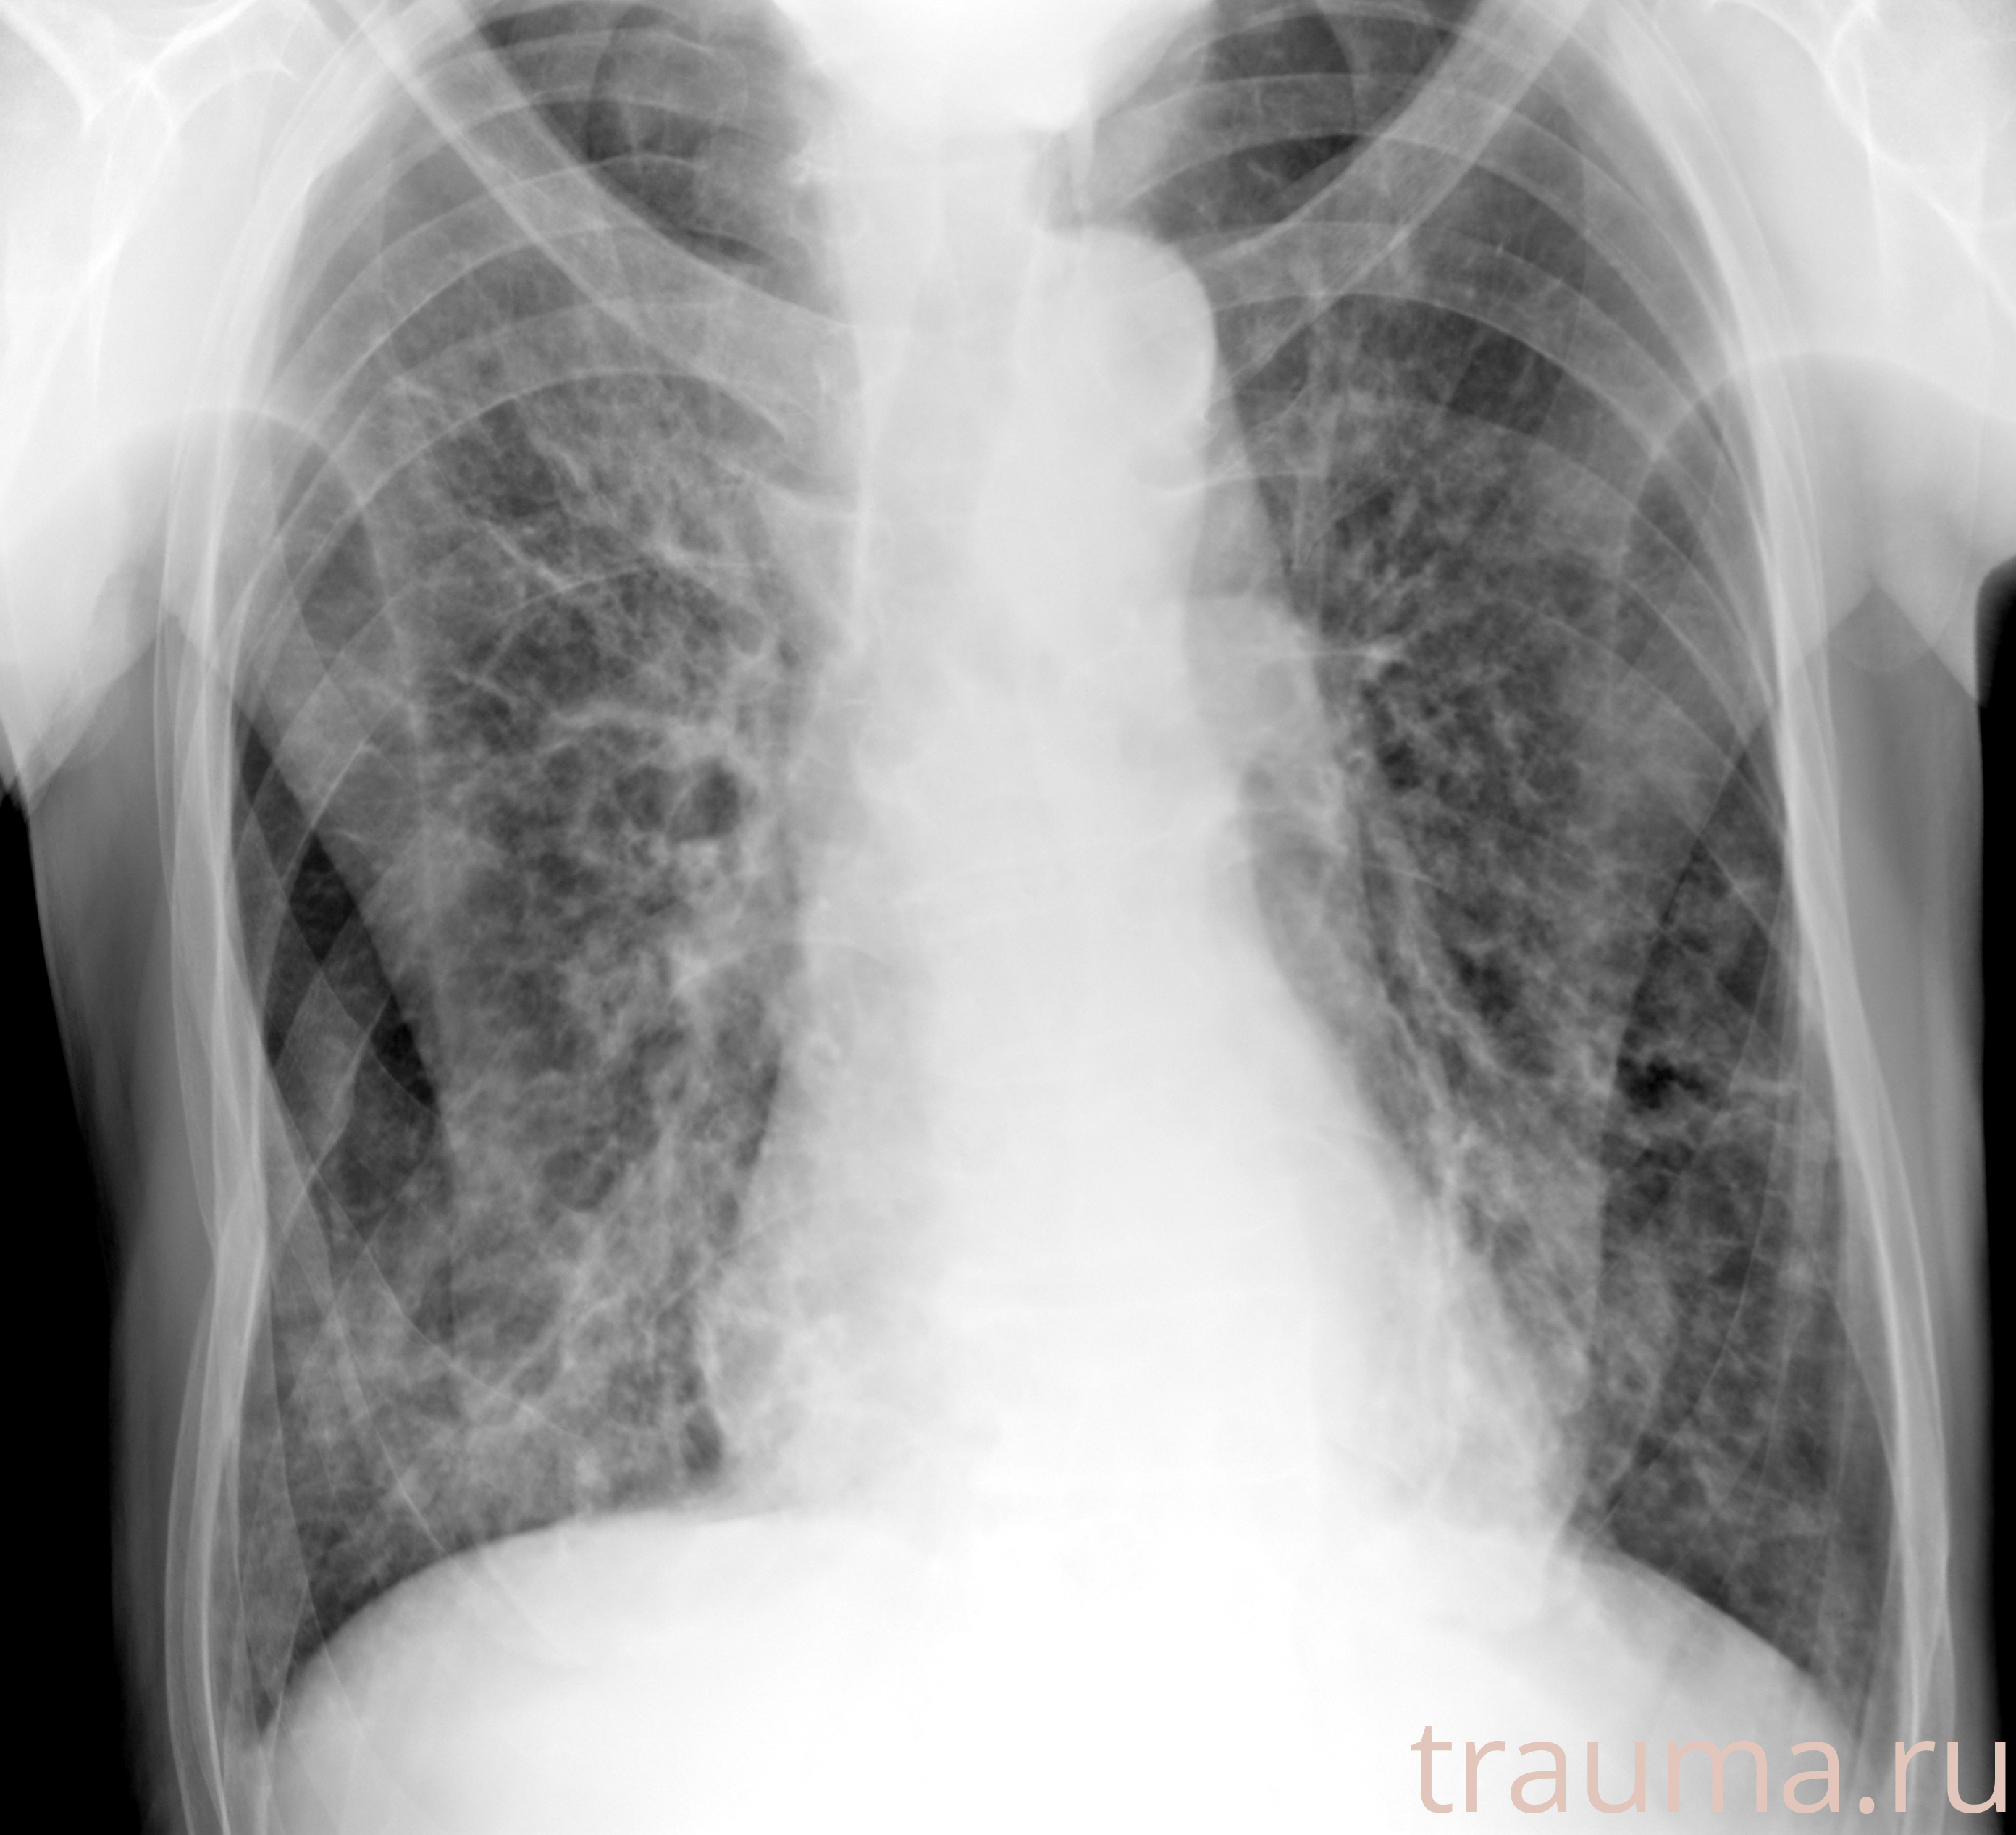

Рентгенограммы

Рентген на дому: по вашему адресу приезжает врач-рентгенолог, травматолог-ортопед с мобильным рентгеновским аппаратом, проводит диагностику травмы или заболевания, делает необходимые рентгенограммы, дает рекомендации по дальнейшему лечению. Получить качественные снимки в домашних условиях возможно благодаря уникальной методике, разработанной МосРентген Центром для института  Склифосовского